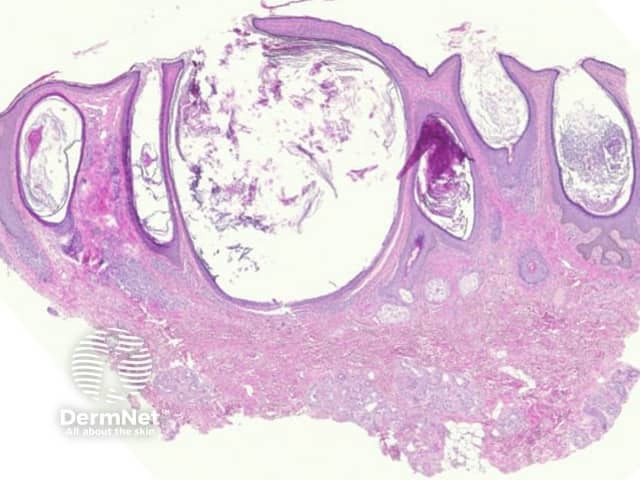

Comedones are follicular retention cysts which may open directly to the surface (open comedone or “blackhead”) or have a blocked surface (closed comedone or “whitehead”).

Sections of open comedones show massive follicular dilation (figure 1). The dilated follicles are filled with keratin (figure 2). These may be filled with cellular debris and/or inflammatory cells. Closed comedones do not show a patent follicular channel to the surface (figure 3).

Figure 1